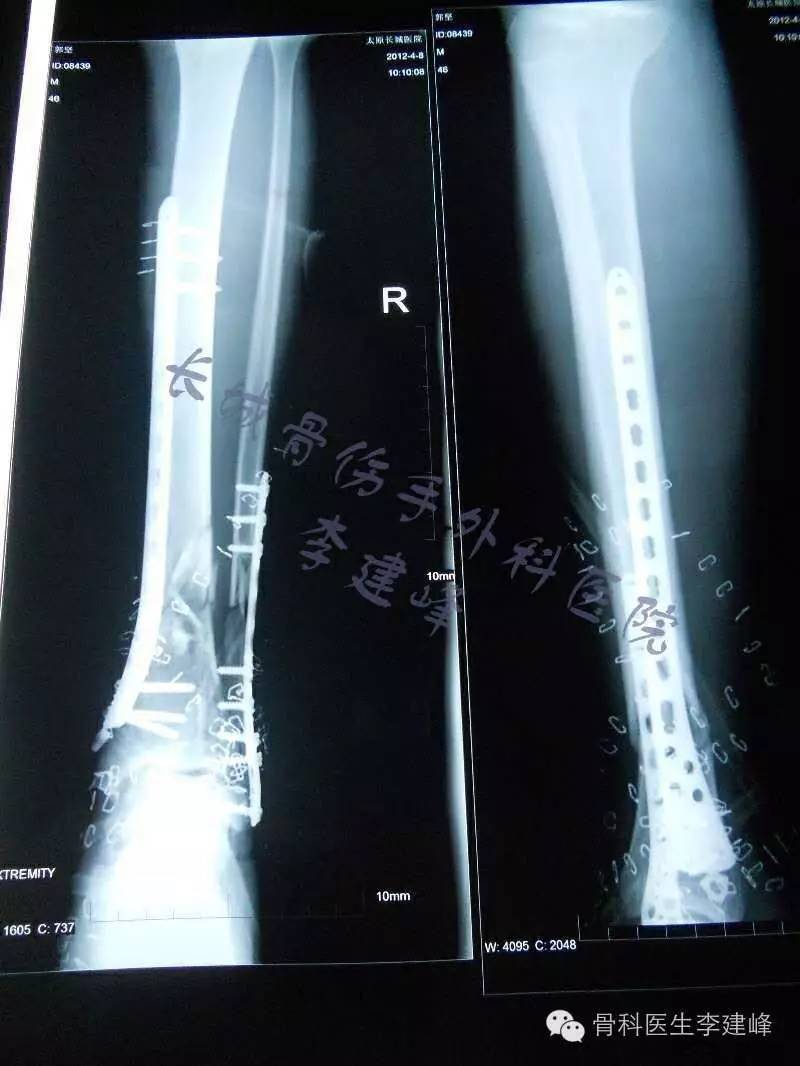

股骨远端骨折锁定钢板固定术后14月骨不连 影像资料清晰 连贯 请老师们多指点 骨科专业讨论版 丁香园论坛